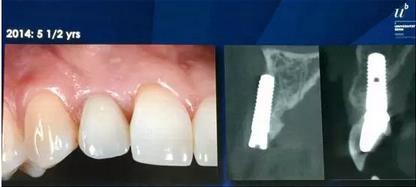

5年半以后的修復(fù)效果非常穩(wěn)定。放射線片顯示種植體周圍穩(wěn)定的骨緣水平以及充足的頰側(cè)骨板。這是術(shù)前和術(shù)后的CBCT對比圖。